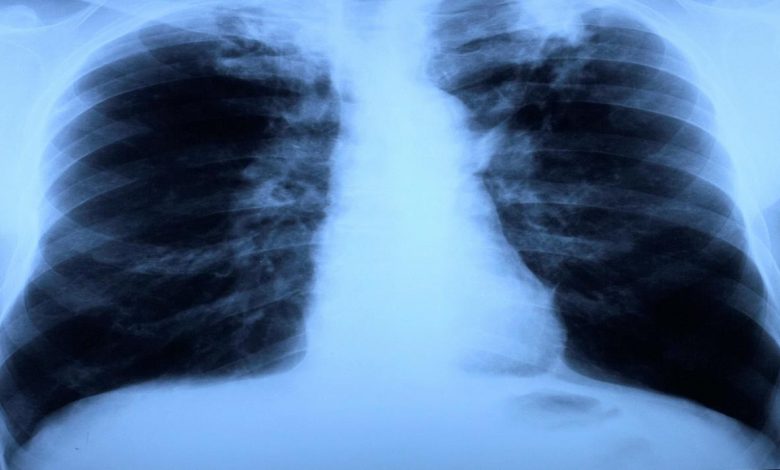

وأشار مولر إلى أن أزمة كورونا أدت إلى انتكاسات كبيرة في القضاء على مرض السل، موضحًا أن الكوادر الطبية والأدوية لم تعد متوفرة، وقال: “كل 22 ثانية يموت شخص بسبب مرض السل، و95% منهم في البلدان النامية والصاعدة.. يمكننا ويجب علينا تجنب ذلك، لأن مرض الرئة يمكن علاجه بمساعدة المضادات الحيوية”.